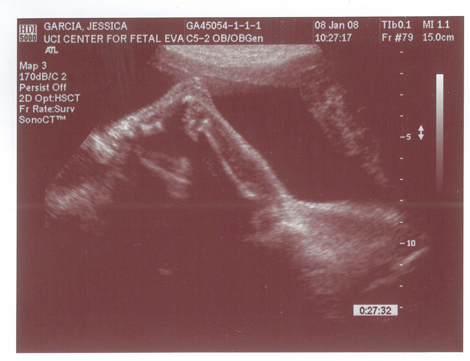

Yes we got a new dsmer coming into the world soon. We got our ultrasound today and its gonna be a boy. And shes a lot further along then we had originally thought. Shes due on April 15th which puts her at almost 6.5 months, (and really not showing it.) He weighs currently ~2lbs. He even opened his mouth while on camera which was really cool.

Here are the pics.

Pic 3: NWS Baby Penis! lol